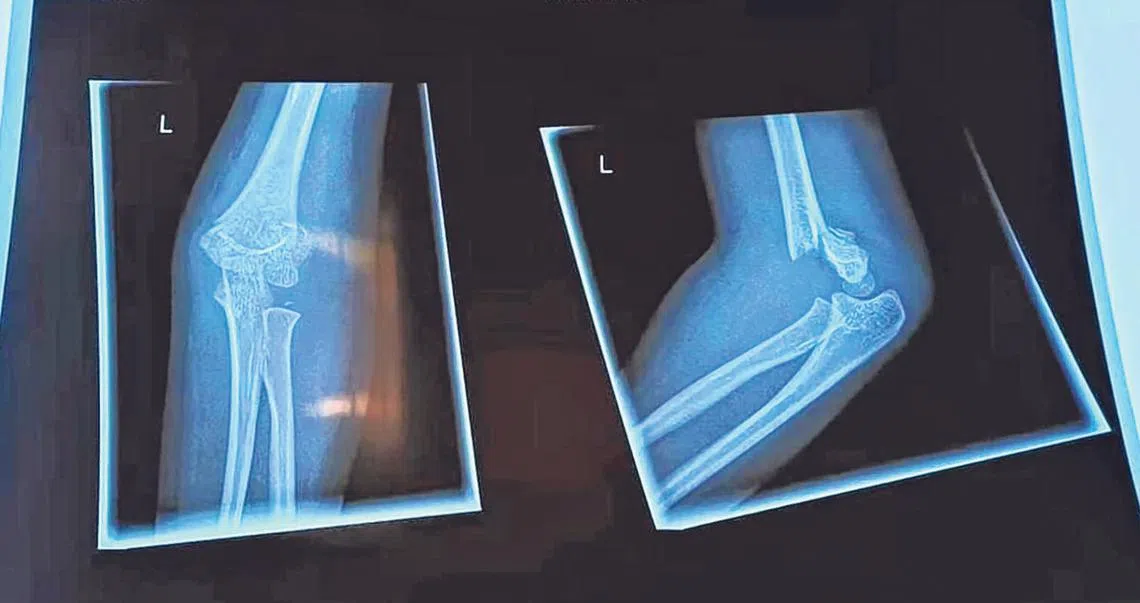

小年夜在顾客络绎不绝的超市外,四岁女童疑被步出超市的妇女勾到脚绊倒,结果左胳膊骨折,须戴护套长达三个月,一家人年夜饭泡汤。

住在新山的他说,女儿在本地没有医药保险,只好在医生的同意下,转到新山私人医院继续治疗。他指女儿在大年初一(10日)当天动手术,隔天出院,这也导致一家三口的团圆饭泡汤。